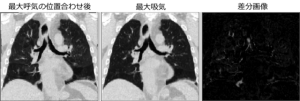

今回は、非線形な画像変換を用いた位置合わせを紹介します。線形あるいは非線形な変換とは、どういう意味でしょうか? まず、平行移動と回転だけを用いた位置合わせは、形が変わらない(剛体)ので、「剛体位置合わせ」と呼ばれます。また、平行移動と回転だけでなく、拡大・縮小等の変形も含まれるアフィン変換は、形が変わっている(非剛体)ので、「非剛体位置合わせ」と呼ばれます。しかし、両者とも変換前後の座標の関係は、下のような線形変換な表現行列(アフィン変換行列)で表されるので、「線形変換による位置合わせ」と言えます。 一方、上のような線形変換な表現行列で表すことができないような画像変換による位置合わせを「非線形...